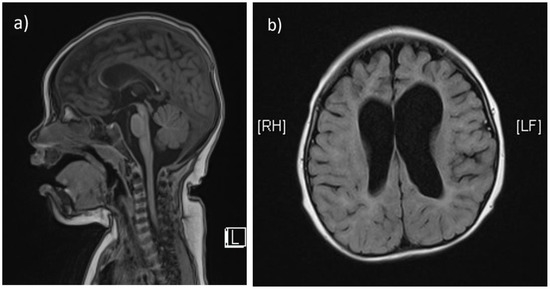

The second child (Patient 2) is a 2-year-old girl born at 39 + 6 gestational weeks via natural vaginal delivery, with a birthweight of 3800 g. Her prenatal and perinatal birth histories were unremarkable. She was initially brought to the hospital at around 12 months due to motor delay, as she was able to roll over, but unable to crawl, stand or stay sitting up unassisted. At 18 months, frequent seizures developed, ranging from focal to generalized tonic-clonic seizures, with irregular intervals (minutes to hours). Subsequently, a marked deterioration of muscle tone and neurologic regression was noted. She no longer smiled and became impassive to surroundings. She had no visual tracking and occasional nystagmus. She could produce vocal sounds without words. Laboratory test showed mild elevation of aspartate aminotransferase (37 IU/L) and CK (335 IU/L). EEG showed slow wave activities. A brain MRI performed at 12 months revealed hypoplasia of corpus callosum and prominent enlargement of cerebral cortical sulci and ventricles (Figure 2a,b). The patient and her family were referred for genetic survey after two consecutive probands suffering from similar debilitating neurodegenerative phenotypes at infancy. The clinical presentations of patient 1 and patient 2 are summarized in Table 1.

Figure 2.

The T1-weighted, sagittal section of brain MRI from patient 2 also shows marked thinning of the corpus callosum (a). The T2-weighted, axial section shows prominent enlargement of cerebral cortical sulci and ventricles (b).